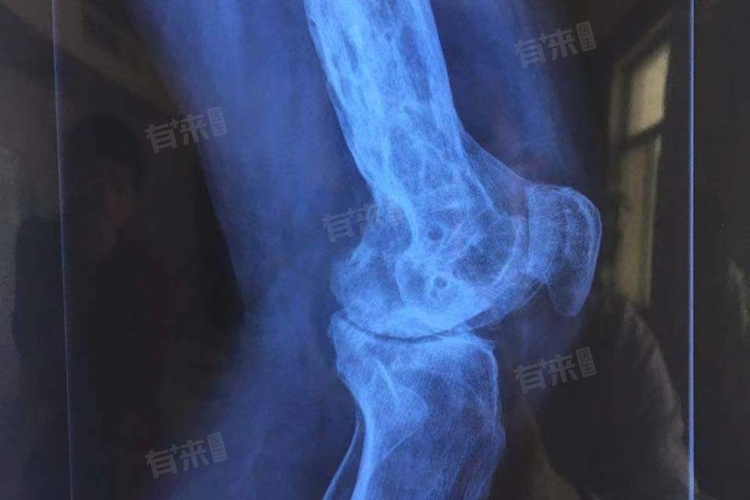

骨折畸形愈合是指骨折在愈合过程中,由于多种原因未能按照正常的解剖位置进行连接,导致骨折端出现成角、旋转、重叠或侧方移位等畸形的一种愈合状态。

- 外观畸形:骨折部位可能出现明显的弯曲、旋转或短缩等畸形,影响外观。

- 功能障碍:畸形愈合可能导致关节活动受限、运动不协调等功能障碍,影响患者的日常生活和工作。

- 疼痛:畸形愈合还可能引起骨折部位的疼痛。